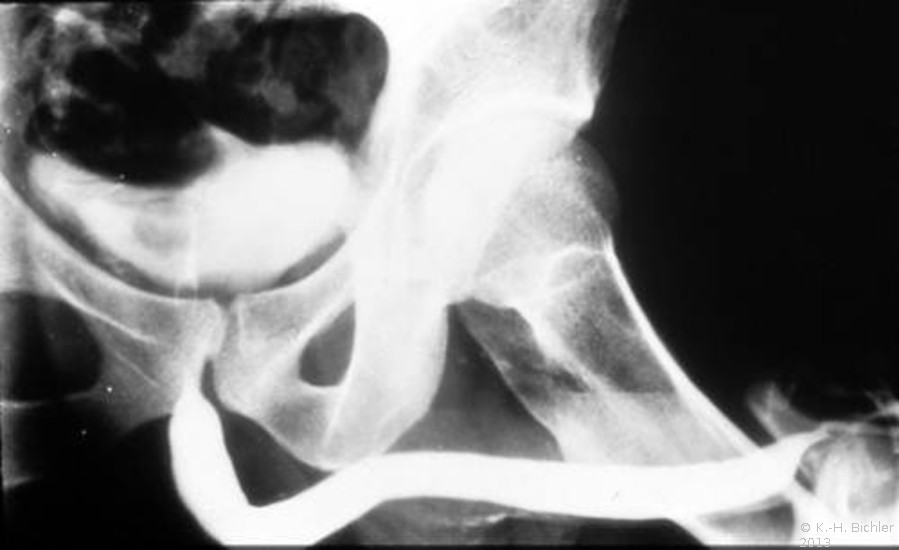

Nach Füllung der Blase mit einem Kontrastmittel, immer mittels Katheter (z.B. via suprapubischen Katheter) wird die normale Miktion unter Röntgendurchleuchtung beobachtet. Damit ist auch eine funktionelle Aussage möglich, ebenso werden pathologische Strukturen im Bereich der Urethra erkannt.

Für die Diagnostik eines vesikoureteralen bzw. -renalen Refluxes ist ebenfalls das MCU erforderlich. Es kann röntgenologisch nach Kontrastmittelfüllung der Harnblase oder nuklearmedizinisch mit radioaktivem Kontrastmittel erfolgen (Abbildung HG1).

Einspritzen von Kontrastmittel entgegen der physiologischen Flussrichtung des Urins in die Harnröhre. Damit werden speziell Strikturen der Harnröhre bildlich dargestellt.